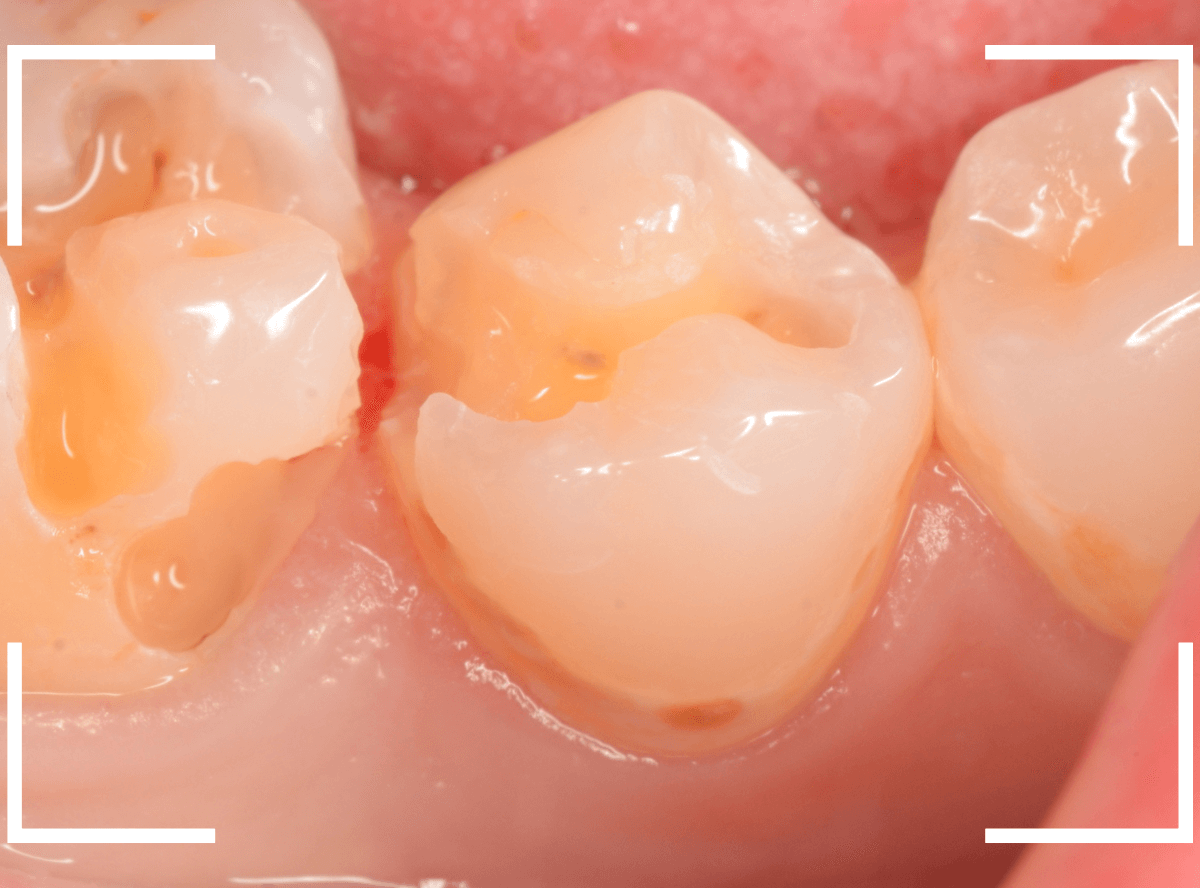

Case.17 レントゲンにはっきり写らないレジンの中の虫歯を削って調べる2

今回も、下の奥歯の虫歯を治療した例です。

特に症状はありませんが、以前に治療したレジンが劣化してすり減っているのと、少し中が黒く透けて見えて、虫歯になっているのが怪しいです。

青いラインが歯の神経です。

以前の虫歯が深めだったようで、レジンが深めにつめてあるのがわかります。

その下がうっすらと虫歯っぽい影になっています(赤いライン)。

虫歯になっているか微妙なラインですが、レジンも劣化していますので、患者さんにご説明して治療することになりました。

レントゲンで虫歯と思われる部分をレジンを除去しました。

見た目には虫歯かどうかはっきりわかりません。

う蝕検知液で染め出します。

うっすらと赤く染色されました。

レントゲン写真と同じく、レジンの下で静かに虫歯が進行し始めていたようです。

もともと深めの虫歯だった部分なので、早いうちに治療が進められてよかったです。

全てのレジンと虫歯を除去しました。

お薬をつめて、症状が出ないかしばらく経過観察します。

歯の外壁部分も薄くなってますので、レジンでは長期保存は難しいと思われます。

今回は、インレーで最終修復する予定です。